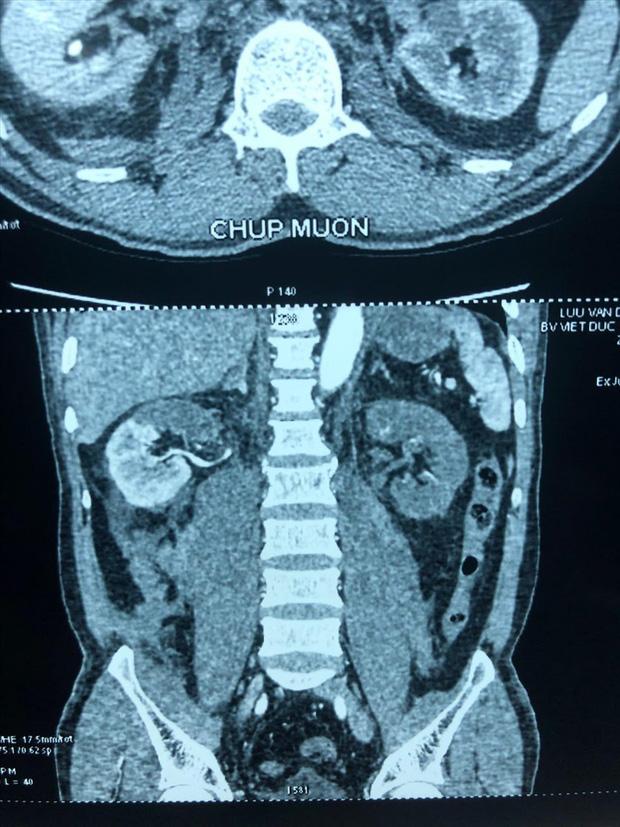

Phim trước mổ của người bệnh, thận phải mất 1/2 chức năng, thận trái mất hoàn toàn. Ảnh: BVCC